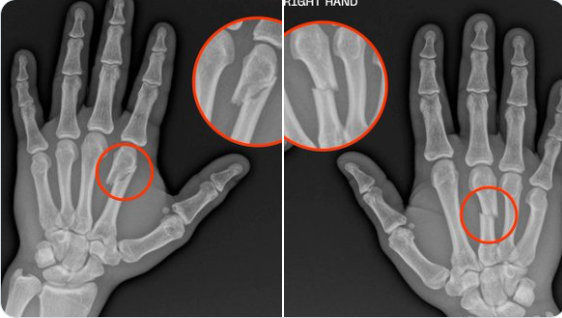

Бразилският ММА боец Жеан Силва е счупил и двете си ръце в последната си битка. 27-годишният Силва се би с Дрю Добър на галавечерта нa UFC в Колорадо, която се проведе миналия уикенд. Силва успя да спечели с технически нокаут в 3-тия рунд.

Победата беше 11-та поредна за него в MMA и 3-та в UFC. Жеан се представи много силно, а сега се появява информация, която още повече издига победата и представянето му. Оказа се, че Силва е счупил и двете си ръце в битката с американеца.

Победата над Добър беше 3-та за Силва през 2024 година. Той играе атрактивно и се превръща в опасност за всички в лека категория. В социалните мрежи Жеан разкри, че счупването на ръцете му е станало още в първия рунд.

Ето снимки: